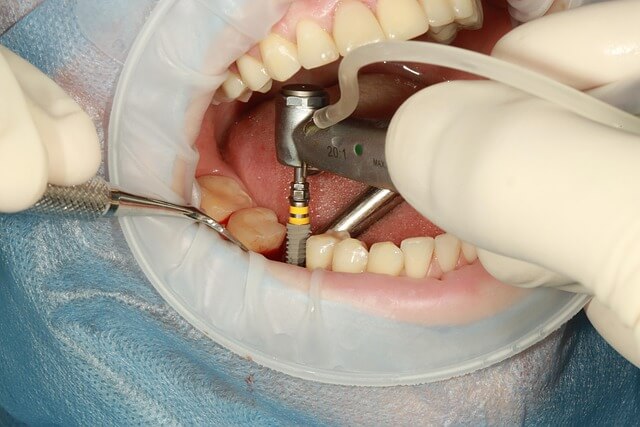

초보자도 쉽게 이해하는 임플란트 뼈이식 핵심 기술! 임플란트 시술을 위한 단단한 기반, 바로 뼈이식입니다. 잇몸 뼈가 부족해서 고민인 분들, 걱정 마세요. 임플란트 뼈이식은 부족한 뼈를 내 몸과 같은 특성의 재료로 채워 넣어, 임플란트를 안정적으로 자리잡게 하는 필수 시술입니다. 이 과정을 통해 튼튼하고 오래가는 임플란트를 경험할 수 있죠. 뼈가 약하거나 잇몸 상태가 좋지 않은 분들도 자신 있게 선택할 수 있는 맞춤형 해결책입니다. 임플란트 뼈이식! 더 이상 고민 말고 지금 바로 확인하고 상담 예약하세요.

*임플란트 뼈이식은 문제를 해결할 수 있는 확실한 방법입니다. 많은 환자들이 임플란트 뼈이식을 통해 튼튼한 뼈를 확보하고 안정적인 임플란트 식립에 성공했습니다.

*임플란트 뼈이식은 잇몸뼈가 부족해도 특수한 재료와 정밀한 시술로 본인 뼈와 같이 건강한 상태를 만들어주어 오래가는 임플란트 기능을 가능하게 합니다.